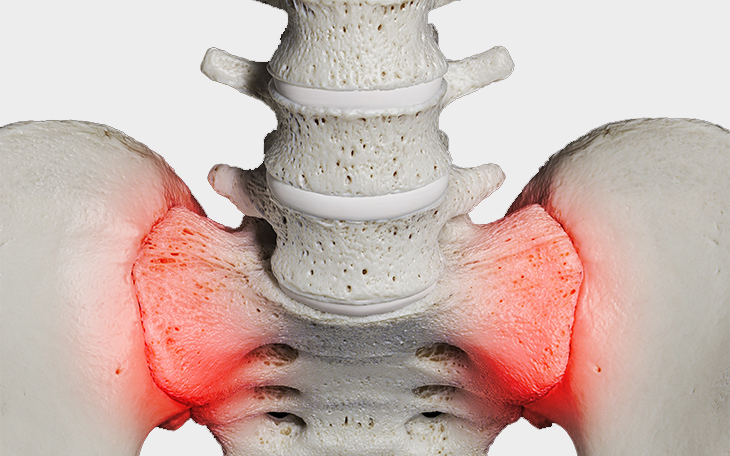

Überblick

Das Iliosakralgelenksyndrom (ISG-Syndrom) bezeichnet schmerzhafte Funktionsstörungen im Bereich des Iliosakralgelenks (ISG) – der Verbindung zwischen Kreuzbein (Os sacrum) und Darmbein (Os ilium).

Obwohl dieses Gelenk nur eine geringe Beweglichkeit aufweist, spielt es eine zentrale Rolle in der Kraftübertragung zwischen Oberkörper und Beinen. Die Beschwerden entstehen meist durch Fehlbelastungen, Blockierungen oder Entzündungen und zählen zu den häufigen Ursachen für tiefsitzende Kreuzschmerzen.

Symptome

• Tiefsitzende Kreuzschmerzen (einseitig oder beidseitig)

• Ausstrahlung in Gesäß, Leiste, Oberschenkel